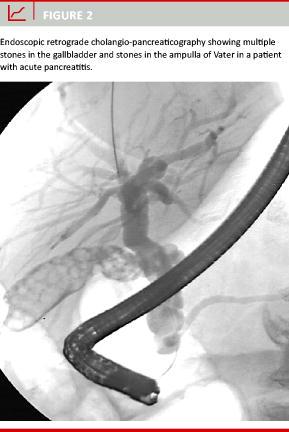

For gallstone to be registered as the cause of pancreatitis required findings of stones in the biliary system either by abdominal ultrasound scanning (US), cholecystography, cholangiography, computed tomography (CT), magnetic resonance cholangio-pancreaticography (MRCP), endoscopic retrograde cholangio-pancreaticography (ERCP) or surgery (Figure 2). The notification "possibly biliary" was applied in cases with unverified suspicion of gallstones, e.g. when: 1) the clinical picture was consistent with gallstone but US was unable to visualise stones or was not performed, 2) the radiological findings were uncertain, or 3) ERCP raised suspicion of a passed stone. For alcohol to be registered as the cause of pancreatitis required that the patient had a high consumption of alcohol (> 50 g alcohol per day) up to the admission and that no other aetiology could be demonstrated. The notification "possibly alcoholic" included patients with pancreatitis in whom alcohol was recorded by the discharging doctor as the most probable cause.